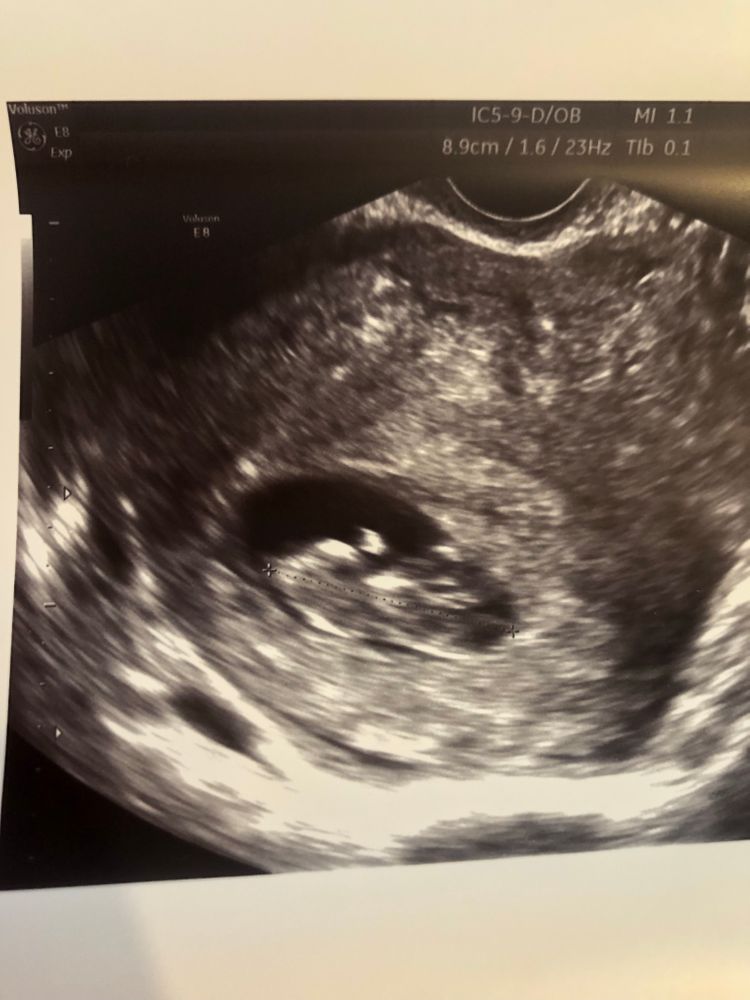

Узи 12 недель! Мальчик?

На узи предположили мальчика на 90%, судя по изображению как бугорок этот смотрит вверх, очень похоже на то. Но были ли у кого то ошибки в определении пола? Есть ли вероятность что ошибка?

Чашка утреннего кофе

На фото у вас не половой бугорок, мне кажется, а скорее пуповина 🤔 слишком уж вверх торчит, странный угол. Но, если узист так уверенно предположил мальчика, то, наверное, мальчик и есть)

Чашка утреннего кофе, вот меня тоже угол смущает😂

пока ехала домой, была уверена что будет мальчик, потом начала рыться в интернете и все, сомнения опять😅😅😅😅

Екатерина, ну узисту-то явно виднее было, там во всех ракурсах, а у вас только фото, где может быть не видно/не понятно) Если предположил, да ещё с вероятностью 90% - были на то основания, наверное)